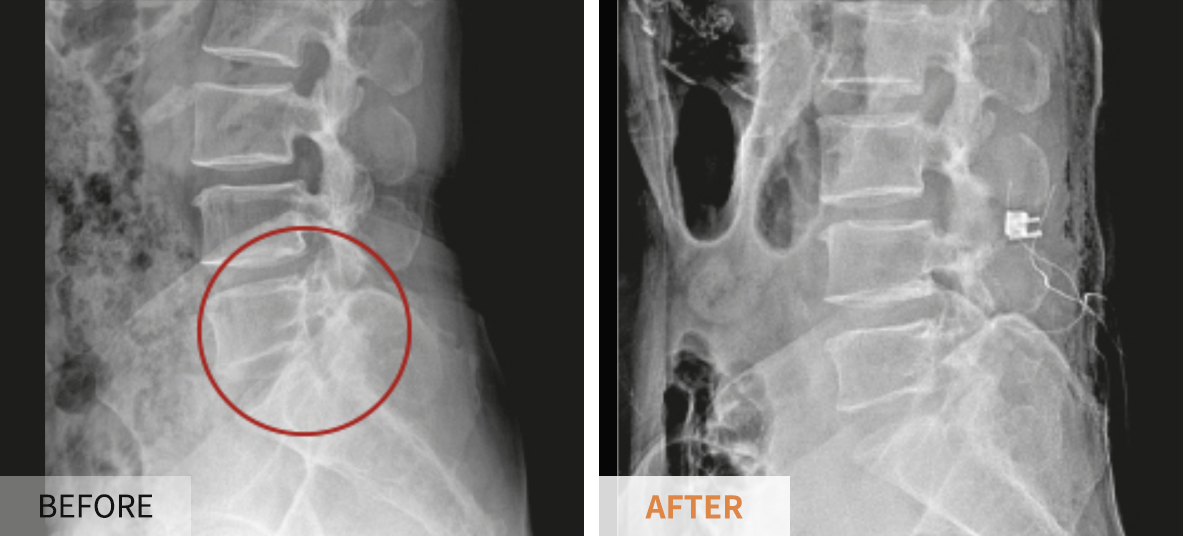

- 수술 고려: 신경 손상이 심하고 보존적 치료에 반응이 없을 때만 고려